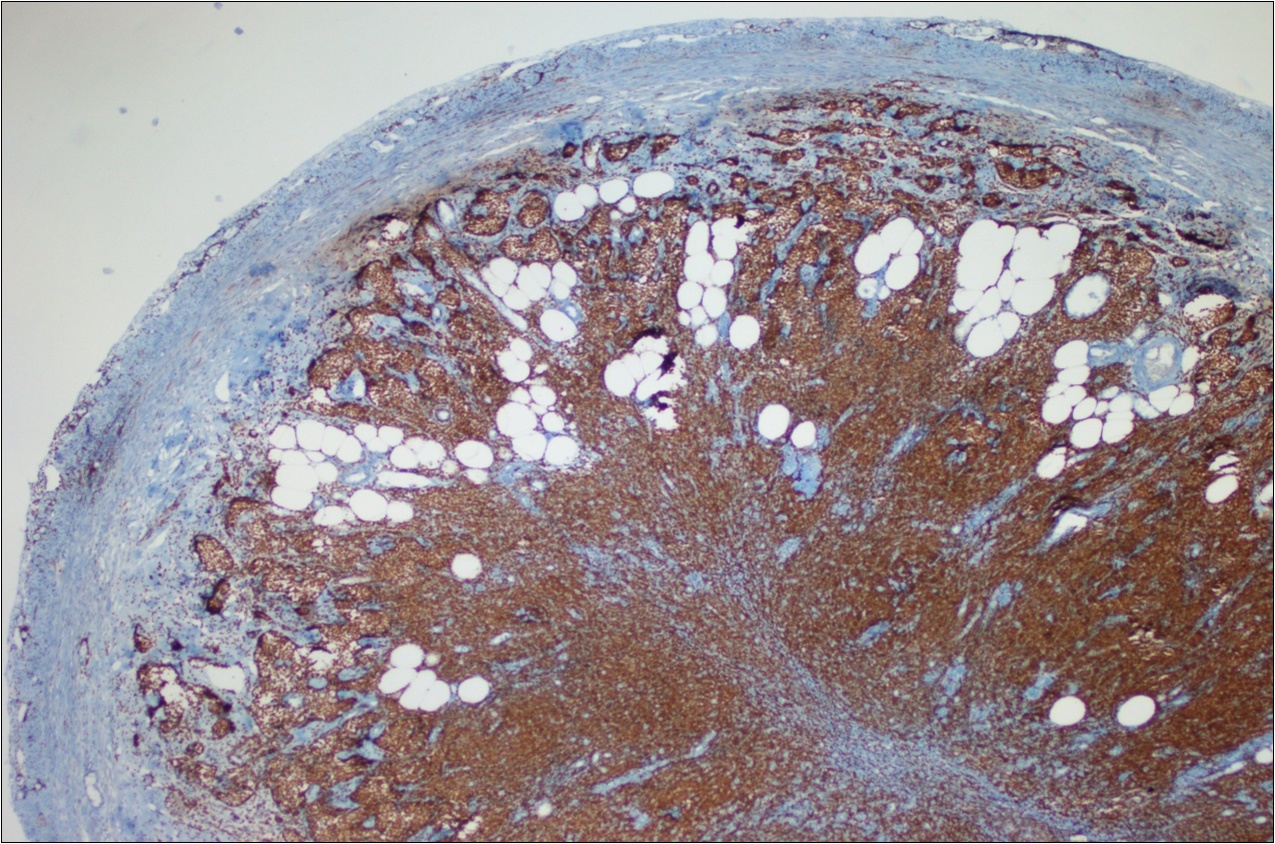

A 63-year-old woman presented to the Department of General Surgery as an outpatient with abdominal pain. Physical examination showed the signs of acute appendicitis and appendectomy was performed. During microscopic examination, a small focus of atypical monotonous lymphoid cell population was seen and the material was sampled totally. The pathological examination revealed MALT lymphoma (Figure 1), with diffuse positivity of cluster of differentiation (CD) 20 (Figure 2), CD 79a and B-cell lymphoma (Bcl- 2) (Figure 3) with just a few CD3 positive lymphoid cells. However, no evidence of adenocarcinoma was found in the appendectomy specimen. After the diagnosis of lymphoma, a complete colonoscopy was planned and this revealed a solid tumoral mass in the caecum measuring 5x4x4 cm. Computed tomography of the abdomen and pelvis revealed mesenteric lymphadenopathy associated with a mass in the caecum with multiple nodules in liver consistent with metastasis (Figure 4). Frozen sections were not obtained since the treatment method would not be affected. The patient underwent anterior resection with regional lymphadenectomy, with the pathological assessment of the resected specimen revealing a collision tumor consisting of a poorly differentiated adenocarcinoma extending through the muscularis propria with MALT lymphoma (Figure 5). Microscopic evaluation of the 11 regional lymph nodes in the mesentery of the resected colon and liver biopsy showed diffuse infiltration of MALT lymphoma with metastasis of adenocarcinoma (Figure 6). According to immunohistochemistry, atypical lymphocytes were positive for CD 20, Bcl-2, and negative for CD3, CD5, CD10, CD23, Bcl-6, terminal deoxynucleotidyl transferase, and cyclin D1. The proliferation fraction (MIB-1 immunostaining) was approximately 20%. The morphological and immunohistochemical findings were used to confirm the diagnosis of synchronous presentation of MALT lymphoma and colon adenocarcinoma within the caecum, mesenteric lymph nodes and liver metastases.

Figure 2.CD 20 positivity of lymphoid cells (CD20, x200)

Figure 3.Bcl-2 positivity of lymphoid cells (Bcl-2, x200)